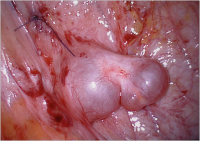

Transplantation of Frozen Thawed Ovarian Tissue – State of the Art